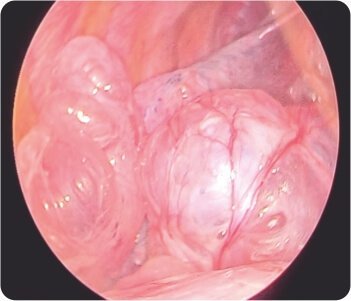

In view of the risk of recurrent pneumothorax, the patient was taken up for VATS (Video Assisted Thoracoscopic Surgery) with right sided bullectomy was done. During the hospital stay, the patient was closely monitored and the patient’s condition gradually improved and was discharged after being stabilized.

Video-assisted thoracoscopic surgery during procedure